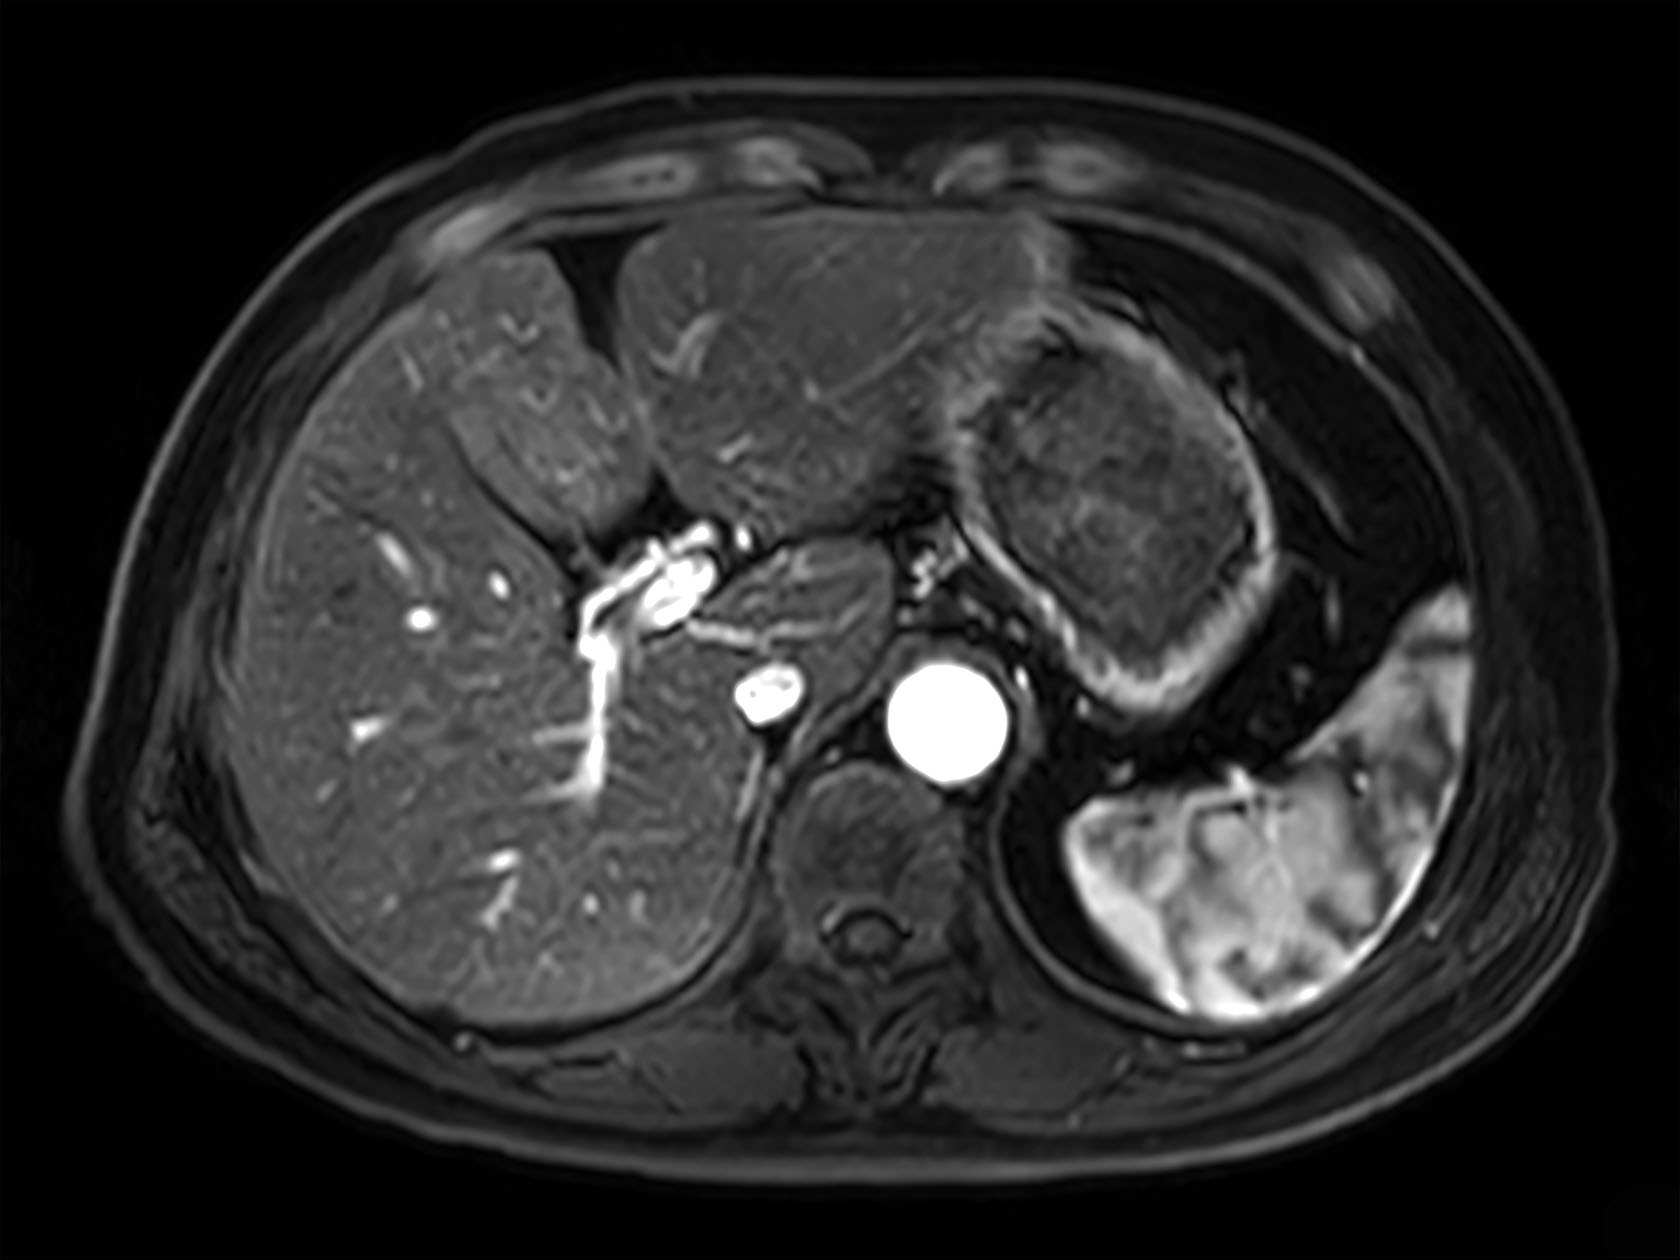

dyn mDIXON XD FFE  (post gado, arterial phase)